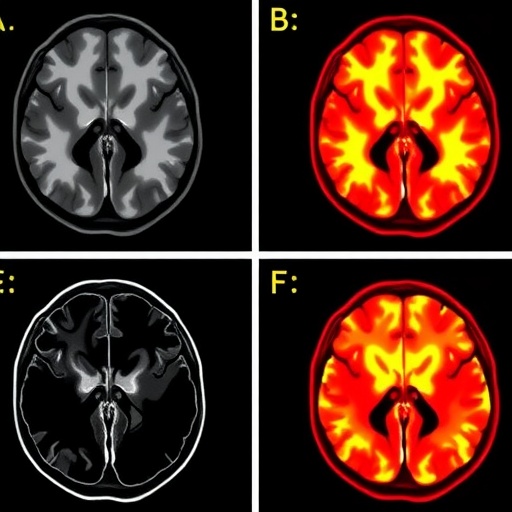

Contrary to a uniform receptor modulation hypothesis, results demonstrated highly region-specific patterns of AMPAR density alteration in patients with TRD. Baseline scans revealed extensive dysregulation of AMPAR throughout cortical and subcortical structures when compared to healthy brains, signifying foundational glutamatergic impairments in depression. Post-ketamine imaging disclosed that symptom improvement correlated with pronounced increases in AMPAR density within selective cortical regions known for higher-order cognitive and affective functions. Simultaneously, decreases in AMPAR density were identified in the habenula, a critical node in reward processing and aversive signaling, highlighting an intricate bidirectional regulation linked to therapeutic outcomes.

This spatially nuanced modulation underlines ketamine’s ability to recalibrate neural circuit dynamics by selectively enhancing excitatory synaptic signaling where deficits prevail, while dampening overactive pathways implicated in maladaptive reward responses. The findings support a model wherein ketamine’s antidepressant efficacy emanates from its capacity to rebalance glutamate receptor distribution and synaptic plasticity across discrete brain networks, thereby restoring functional connectivity and alleviating depressive symptoms rapidly.